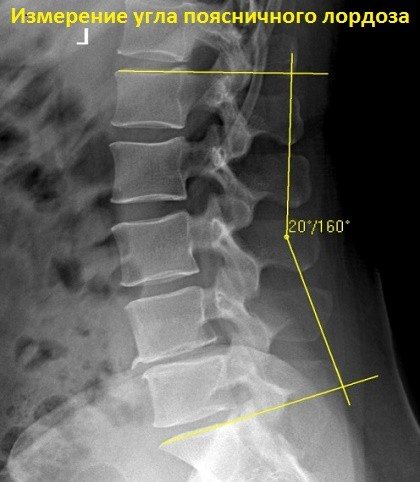

Ребенок рождается с прямым позвоночным столбом, и только когда он начинает учиться сидеть, появляется вначале изгиб в поясничном отделе, а затем, для равновесия, и все остальные «вогнутости». Вот этот изгиб поясничного отдела, пока он находится в пределах 150-170° (по рентгенограмме, КТ или МРТ в боковой проекции) – это физиологический поясничный лордоз. Как только этот угол уменьшается или увеличивается, лордоз получает название патологического.

Если его угол менее или равен 145 градусам, это гиперлордоз, если же более 170 градусов – гиполордоз.

Если поставлен диагноз «лордоз позвоночника сохранен», значит, искривление соответствует норме, то есть угол находится в переделах 150-170°. Однако даже при этом существует вероятность развития болезни позвоночного столба. При воздействии неблагоприятных факторов может появиться патологическое искривление позвоночника.

Другими словами, речь идет о гиперлордозе, то есть угол изгиба слишком выражен, он составляет менее 145°.